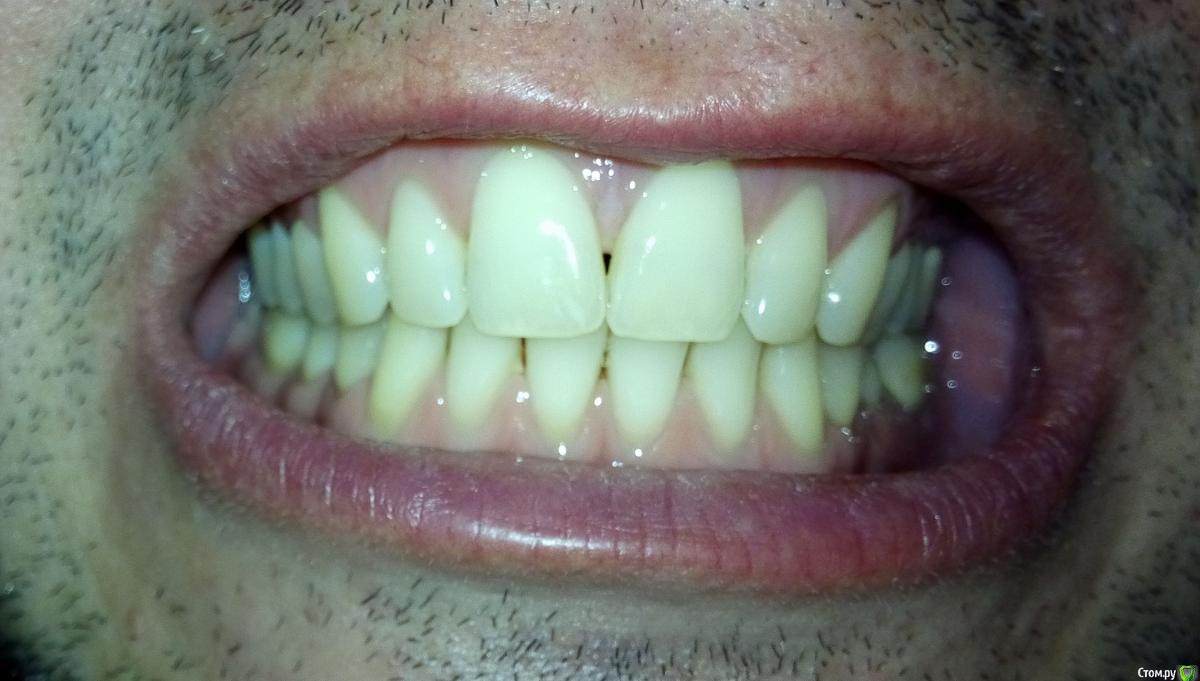

Мне 34 года. В связи с необходимостью перелечивания корней 36 и 37 зубов пришлось заменить металлокерамическую коронку. Однако, она мне не подошла: через несколько дней при смыкании нижняя челюсть начала какбы съезжать впред и влево, начали соприкасаться (ранее такого не было) передние левые зубы. Доктор объяснил это занижнием коронки в области 36 зуба. Сделали новую коронку, которую я носил неделю, но она мне тоже была неудобна (как бы завышала). Ее опять изменили, немного занизили. В результате почти месяц, ношения разных вариантов и в итоге:

* Ни с одним вариантом мне не было удобно. Сейчас не могу сомкнуть зубы, чтоб было удобно сразу и справа и слева как до лечения.

* Дней 14 назад появились боли в жевательных мышцах с обоих сторон. Сейчас болей нет (наверное, благодаря упражнениям описанным ниже), но в внчс справа появились неприятные ощущения и пощелкивания, а слева (где стоит коронка) - похрустывания. Основной дискомфорт в внчс противовположном коронке.

-судя по бугристости на углах нижней челюсти и фасеткам стираемости  на многих зубах , Вы- бруксист! и еще тот!)  отсюда и симптоматика, и боли в мышцах.

Так же могу отметить, что форма старых 36 и 37 металлокерамичких коронок и старых зубов была плоскими (почти ровная площадка), стоматологи это свзязывали с тем, что зубы антагонисты соприкасались бугор-бугор, а не бугор-впадина. Самое инетерсное, что сейчас мне сделали бугры на коронке, которые попадают в впадины, но этот доцент, не зная какими были ранее зубы и коронки, констатировала, что ранее они были плоскими. Может стОит вернуться к старым формам? :wacko: